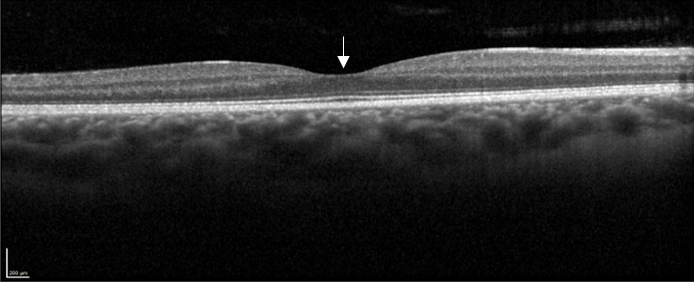

Des rétinophotos couleurs permettent de visualiser la veine concernée par l’occlusion, la présence d’hémorragies intra rétiniennes, de nodules cotonneux etc … L’OCT objective la présence d’un œdème maculaire et de mesurer son épaisseur. Enfin c’est l’angiographie à la fluorescéine qui nous renseigne sur l’état de la circulation du sang dans les vaisseaux rétiniens et la présence de complications ischémiques périphériques.

Coupe OCT maculaire montrant un œdème maculaire cystoïde post OBVR inférieure.

• Tomographie par Cohérence Optique (OCT) : Permet d'évaluer le degré de gonflement rétinien (œdème maculaire), la complication la plus fréquente et principale cause de la baisse de vision.